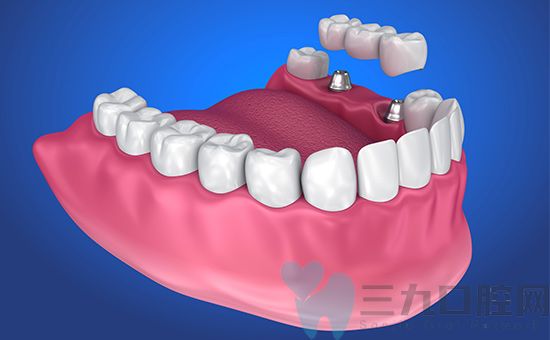

种植牙是一种现代牙齿修复方法,通过植入人工牙根以恢复缺失的牙齿。与传统的义齿相比,种植牙更接近真牙的外观、功能和感觉。

种植牙通过人工牙根与口腔骨骼结合,提供了稳固的支持和牙齿的固定。这使得种植牙能够恢复咀嚼功能,使患者能够正常地咀嚼各类食物。与真牙一样,种植牙可以承受咀嚼过程中的压力和力量。

种植牙的修复体在外形和功能方面与真牙非常相似。它们可以恢复正常的咬合力,帮助维持牙齿的位置和相邻牙齿的稳定性。种植牙能够提供良好的发音能力,并在笑容中提供自然、美观的外观。